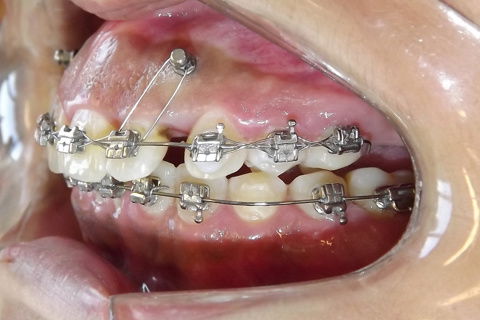

Foto após 22 meses.